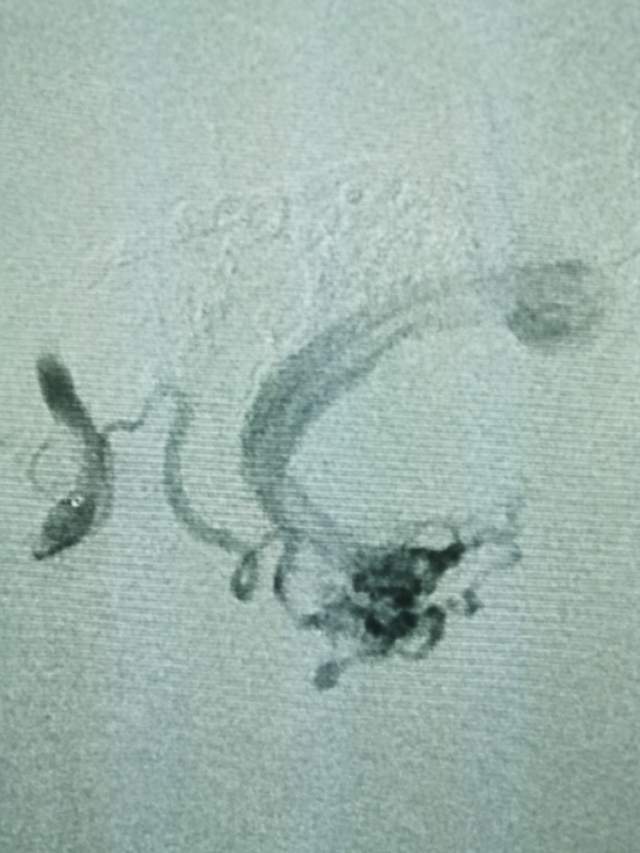

第一次手术:我们先超选6个分支小血管给予栓塞,去其枝叶,保留主干,结构逐步显山露水,清晰可见引流静脉的起始部,为二期手术做足准备~~~